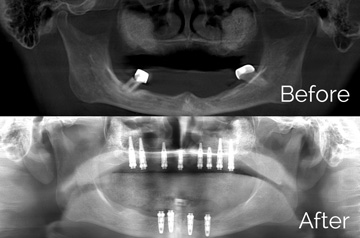

All-on-4 Teeth-in-a-Day™

- Extractions with Alveoloplasty and Immediate Implants

- Temporary Denture Conversion into Temporary Bridge

- Final Restoration by Restorative Doctor